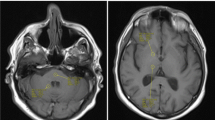

Signal intensity measurements were obtained by applying a circular ROI of 4-mm diameter within the globus pallidus, the dentate nucleus, the thalamus and the pons to the unenhanced T1-weighted images. ROI placement was agreed upon by consensus of two readers (M.C.R.E. and L.F.-T. with 7 years and 11 years of experience in neuroradiology, respectively) blinded to clinical data and to the serial number of the MR scan. In each subject, ROI measurement was conducted once and always placed on the right side. If the right side could not be assessed, then the left side was used (n=4 patients for globus pallidus:thalamus measurement). B0 images from axial diffusion-weighted and axial T2-weighted sequences were always used to guide the correct ROI placement (Fig. 1).

Region of interest (ROI) analysis at axial MRI in a 8 years old boy. a-b For quantitative analysis of globus pallidus-to-thalamus signal intensity ratio, ROIs were drawn in the globus pallidus (white circle) and thalamus (black circle) on unenhanced T1-weighted images (a) using B0 images from diffusion-weighted imaging (b) as reference (arrow in Fig. 1b indicates the globus pallidus). c-d For quantitative analysis of dentate nucleus-to-pons signal intensity ratio, ROIs were drawn on T1-weighted images (c) in the dentate nucleus (white circle) and pons (black circle) using B0 images from diffusion-weighted imaging (d) as reference (arrow in Fig. 1d indicates the dentate nucleus)